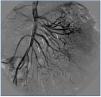

A 26-year-old man presented with a few weeks history of nausea, malaise, blurred vision, a brief episode of visual loss and hypertension. While working, he experienced loss of sight but regained it after a couple of minutes. He had no history of chronical disease. Family history of patient was not contributory-without a family history of vascular disease or hypertension. He was not taking any medications and denied any heavy alcohol, cocaine or intravenous drugs use, but had a 10-pack-year tobacco history. On review of systems, he reported 6-7 kilograms of unintentional weight loss in the past one year. Blood pressure was 150/70mm/Hg, a temperature of 36.8oC, heart rate of 64/min, and respiratory rate of 16/min. Cardiovascular and respiratory system examination was not remarkable. Indirect ophthalmoscopy was performed; retinal detachment (exudative) in both eyes, raised papilla limits, retinal vessel tortuosity, choroidal hypopigmented lesions under retina and superficial haemorrhages were detected. Exudative retinal findings defined as Vogt-Koyanagi-Harada syndrome. Laboratory and ultrasonographic findings were shown at Table 1. Peripheral blood smear revealed; enough platelets with normal morphology, schistocytes were rare, reticulocytes <2%, normochromic normocytic red blood cells. Primary hematological disease was not considered. He was started to be investigated for primary hyperaldosteronism, Cushing's disease and pheochromocytoma. During the follow up in nephrology service, the patient had presyncope, convulsion, hypertensive emergency and altered mental function. His blood pressure was 220/110mm/Hg. Blood pressure was controlled via sodium nitroprusside infusion for 48 hours and amlodipine 10mg, nebivolol 5mg, doxazosin mesylate 8mg at following days in intensive care unit. After the neurology consultation was performed the patient was evaluated with magnetic resonance imaging (MRI). Bulbus, pons and left mesencephalon, basal ganglia, peri-supraventricular white matter areas of increased T2 signal is considered to be consistent with vasogenic edema. Subretinal haemorrhages were detected at posterior parts of both orbit. It was reported as posterior reversible encephalopathy syndrome (Figure 1). After 5 days of intensive care follow up the patient had normal blood pressure. After excluding frequently seen secondary hypertension causes, renal and mesenteric angiography was performed at the same time suspecting renovascular hypertension. Angiography revealed multiple microaneurysms involving the parenchymal branches of the celiac artery, bilateral renal artery and superior mesenteric artery (Figure 2 and Figure 3). After the angiography, eventually, ultrasound-guided renal biopsy was performed. Light microscopy revealed 9 glomeruli with no specific patterns except a slight increase in mesangial matrix. Normal interstisium, tubular focal atrophy and intimal-medial thickening of blood vessels was apparent. Due to increased cellularity obstruction and perivascular fibrosis were found in blood vessels. Histochemically, periodic acid-Schiff, M. Silver, Masson’s Trichrome staining was used. Congo red staining was negative. With direct immunofluorescence method, there was no specific deposition of IgA, IgG, IgM, C3, C4, C1q, fibrinogen, kappa and lambda. Histological diagnosis was reported as signs of vascular myointimal hyperplasia (Figure 4). With all these findings (clinical characteristics such as severe hypertension and renal insuficiency, constitutional symptoms such as malaise and weight loss, inflammatory parameters like elevated erythrocyte sedimentation rate-ESR and C-reactive protein-CRP, angiographic findings) the patient was diagnosed as PAN. Oral prednisolone therapy as 0.5mg/kg/day had been given. But as creatinine levels raised up and hypertension could not be well controlled with drug therapies, eventually hemodialysis was started (Figure 5).

Figure 2. Multiple microaneurysms involving the parenchymal branches of the celiac artery, bilateral renal artery and superior mesenteric artery

Figure 3. Multiple microaneurysms involving the parenchymal branches of the celiac artery, bilateral renal artery and superior mesenteric artery